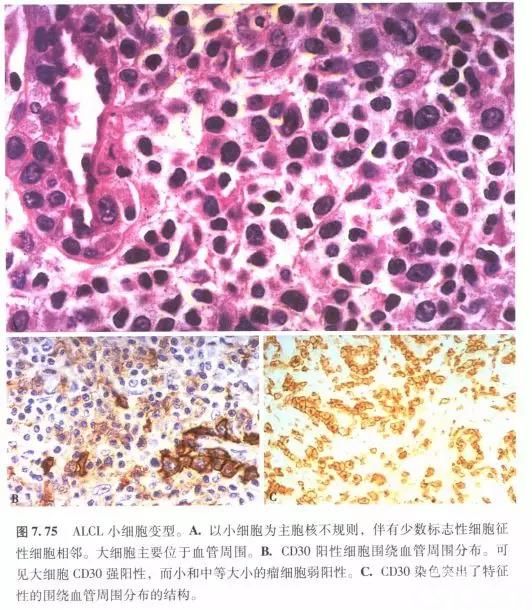

间变性大细胞淋巴瘤,ALK阳性 – 91360智慧病理网

ALK阳性间变性大细胞淋巴瘤 – 慧海拾穗博客 – 华夏病理网博客